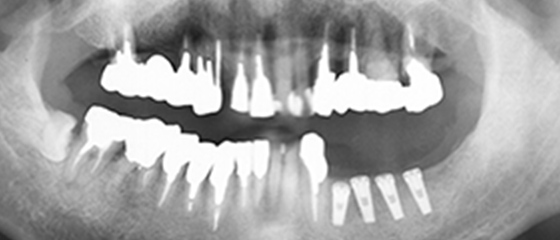

治療経過

オールオン4が存在しなかった2007年当時に、インプラントでの治療を行いました。当初の治療プランとしては、既に欠損している左下にインプラントを施して左側で噛めるようにし、次に崩壊が進んでいる右上にインプラントを埋入、その後に上前歯という順番で噛み合わせの高さと噛む機能を維持した状態で噛み合わせの崩壊を防ぐ、という計画でした。

2000年と2003年の文献で一番成功率が高いと評価されたイノバ社のエンドポアインプラントを使用して治療を行いました。

右下の奥歯

一通り治療が終了した後、右下の奥歯が根の周囲に膿を溜めて強い痛みを起こしたため、抜歯し、インプラントをしました。この時は、国産のGCインプラントを使用しました。

右上犬歯

犬歯ということで大きな負荷がかかった為か、インプラント周囲の感染か、糖尿病のせいか、喫煙の影響か、右上犬歯分のインプラントが脱落したため、インプラントで最も古い歴史を持つブローネマルクインプラントを埋入しました。